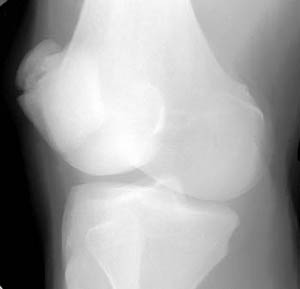

Patellar Fracture

Oblique view |